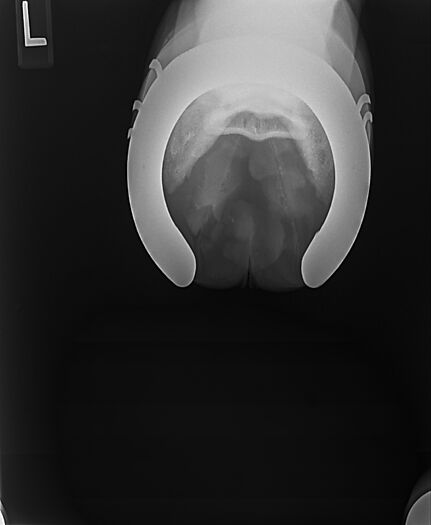

**Tex sells at the Colorado Horse Sale's Best of the West Select Sale on May 30th in Castle Rock, CO - He will complete the riding & handling Sift Exam, baseline veterinary exam, and will sell with 4 total radiographs (DLPMO & Front Foot Lateral)**